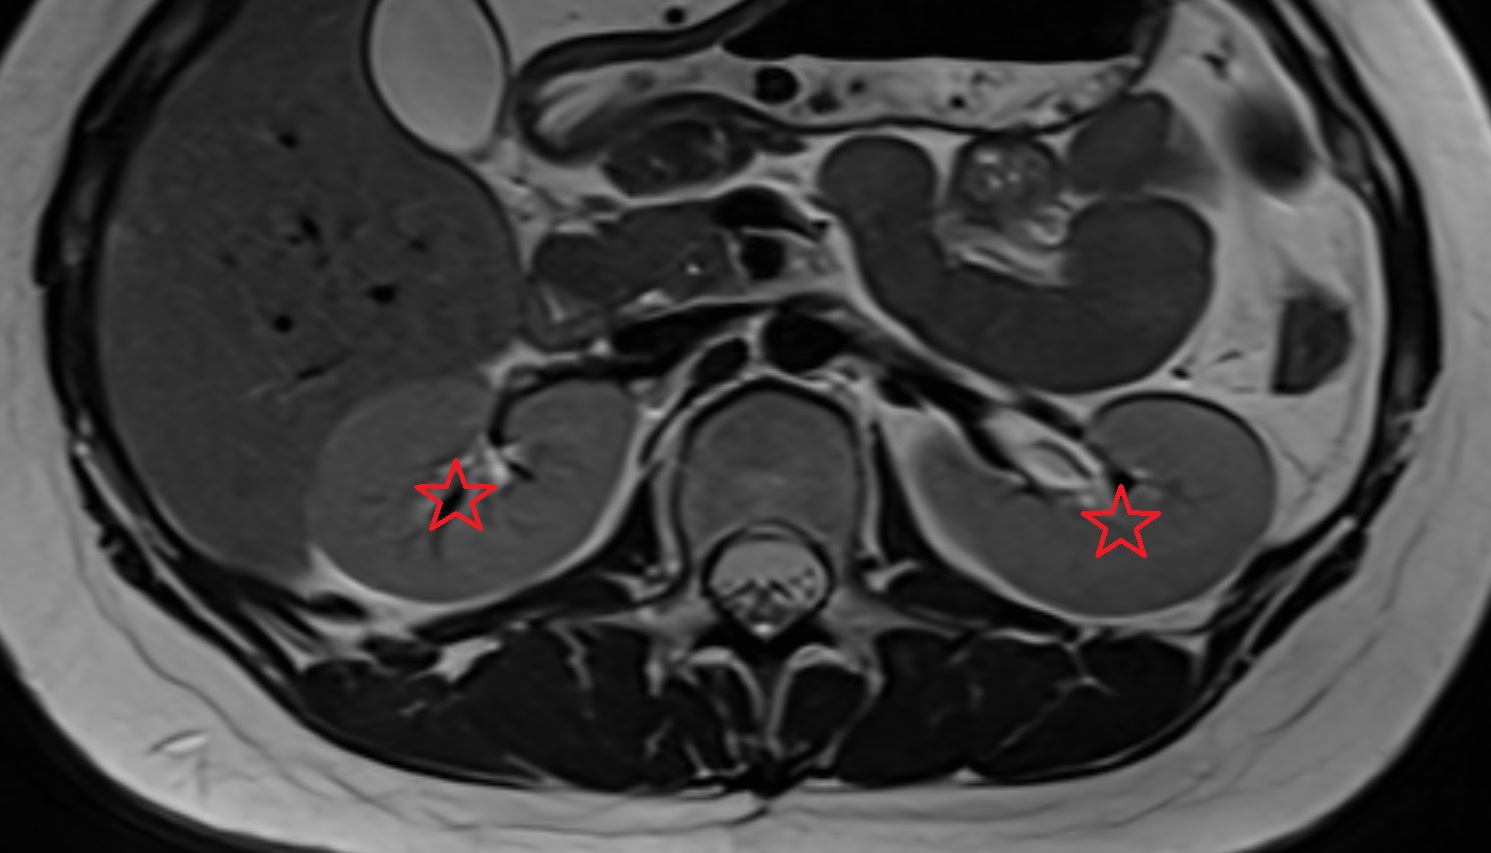

- kidneys

- Right kidney

- Left kidney

- Kidney cortex (Renal cortex)

- Renal capsule

- Renal medulla

- Renal pyramids